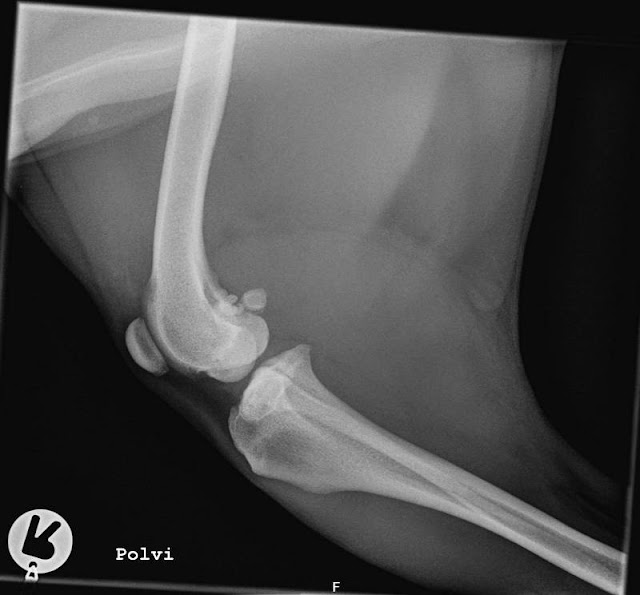

Palpaatiotutkimuksessa todettiin, ettei koira ota oikealle etujalalle täyttä painoa, aristaa kaulan vasemmalle kääntöä nostamalla oikean etujalan ylös. Ei arista eturaajojen nivelten manipulaatiota, eikä arista niskaa. Selkä arka rintarangan lopussa. Kun takapäätä palpoidaan, tulee arkuutta alaselän köyristämisestä, eli koira ei pysty viemään takaraajoja eturaajojen väliin. Oikea kinnernivel täyttynyt. Ontumatutkimuksessa koira reagoi takapolvien taivutukseen menemällä sen jälkeen passiravia ja ympyrällä vielä huonommin."

"Kuvissa todetaan alaselässä L7 - S1-välissä alkavaa spondyloosia."

Vastaus mysteeriin löytyi kontrollista viikon päähän buukatusta CT-kuvasta. Kuvat kävivät Sveitsissä asti jollain spesialistilla, mutta tässä käännettyä diagnoosia: "Bikepsjänteen ura on normaali, eikä bikepsjänteen yläkiinnityskohdassa ole mitään muutoksia. Lievää spondyloosia lannerangan viimeisen lannenikaman (L7-S1) ja ristiluun välissä sekä 5-6 lannenikamien välissä. Ristiluun ja viimeisen lannenikaman (L7) kohdalla spondyloosi leviää sivusuunnassa niin, että nikamien välisissä raoissa (intervertebra foramina) on ahtaumaa. Samoin L7-S1 välissä on välilevyn pullistuma, joka ei kuitenkaan paina selkäydinjatketta. Pienet välilevyn pullistumat näkyvät kolmos-nelos lannenikamavälissä ja vitos-kutos lannenikamavälissä ilman selkäydinjatkeen painetta."

Päätelmä: "Pientä olkapään sisäosan pehmytosavauriota, joka voi johtaa epästabiilisuuteen ja lievään kipuun. Minimaaliset Hansen tyyppi II -välilevypullistumat, ei selkäydinpainetta eikä selkäydinjatkeeseen kohdistuvaa painetta. Voivat välillä aiheuttaa paikallista pientä kipua." (Lisäksi jotain pientä siellä täällä, aavistuksen virheellisen rakenteen aiheuttamaa, iän tuomaa kulumaa jne., lievä lonkkaniveldysplasia ym. jotka ovatkin olleet tiedossa jo > D:n lonkat, joista oikea on vasenta lievempi.) Mutta löytyihän se syy miksi selkä oli edelleen kipeä. Välilevyn pullistuma, joka ei ollut näkynyt röntgenissä, oli varmaan ronkinnasta tai mistä lie ottanut nokkiinsa ja kesti "parantua" ts. lakata aikeuttamasta kipua. Me jatkettiin laserissa käyntiä, mutta nyt ei hoidettu enää olkapäätä vaan ainoastaan selkää.

Parin viikon kuluttua CT-kuvauksesta saatiin luvalla käydä fyssarilla, eikä Tanja meinannut uskoa koko diagnoosin kirjoa sen perusteella miten hyvässä kunnossa Luumu oli. Tuntui ihanalta saada välillä jotain positiivisia uutisia, kun pari kuukautta oli saanut vaan aina käännellä poskea kerta toisensa perään. Lisäksi käynti toi muutenkin lisää perspektiiviä meidän tilanteeseen. Voisihan asiat tosiaan aina olla huonommin. Sillä voisi olla tähän mennessä vaikka kummatkin ristarit leikattuina, ja onhan Luumun elinaikana mennyt meidän koiratuttuja monttuun milloin mistäkin syystä. Pitää olla kiitollinen siitä, mitä kaikkea positiivista kuvauksista löytyi. Lievästä mataluudesta huolimatta lonkat ovat oikein siistit, ja vanhassa traumapolvessa fabella on paloina, mutta siististi paikoillaan. Edelleen, ihan muuttumattomana nelisen vuotta tapaturman jälkeen. Nyt on koko koira tutkittu lähestulkoon päästä varpaisiin, ja tiedetään minkä kanssa sitä ollaan tekemisissä. Ei tarvitse enää elää epätietoisuudessa.